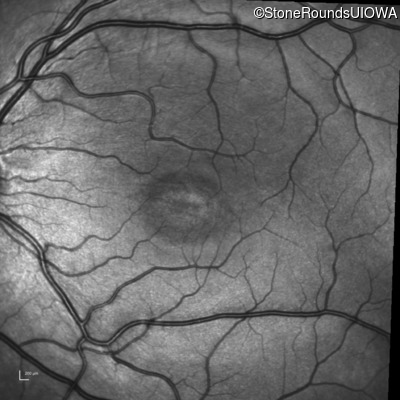

Infrared Fundus Photograph - Right - 20/50

Exemplar